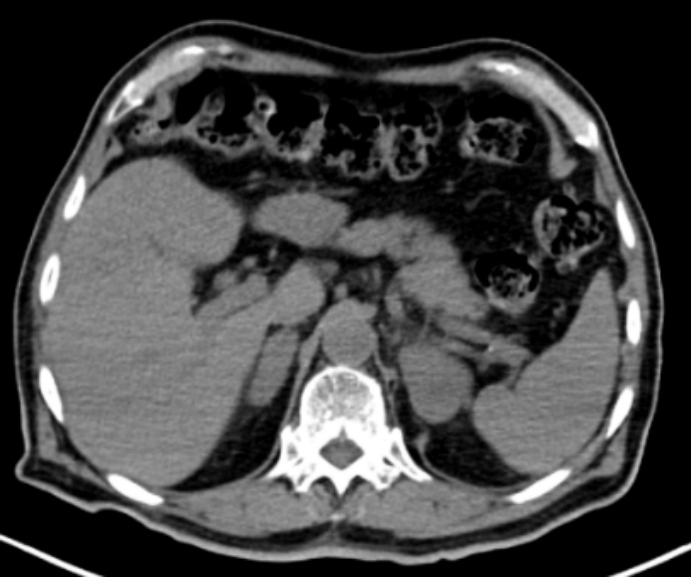

Con el fin de estadificar y caracterizar el comportamiento metabólico de las lesiones descritas en las glándulas suprarrenales, se realizó un estudio 18F-FDG PET/TC que mostró masas adrenales sólidas bilaterales con intenso aumento del metabolismo, sin evidencia de compromiso nodal o extranodal local ni a distancia, compatible con viabilidad tumoral mal diferenciada primaria adrenal bilateral (fig. 3). Dada la ubicación de las masas y sus características por imagen multimodal, se sugirió un diagnóstico de síndrome linfoproliferativo y por decisión multidisciplinaria se realizó adrenalectomía izquierda, cuyo análisis histopatológico e inmunohistoquímico fue compatible con LNH primario adrenal tipo B difuso de células grandes, patrón no-centro germinal (fig. 4).